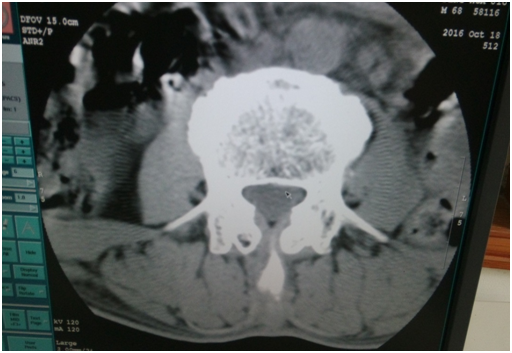

機(jī)器故障:圖像有偽影,無(wú)法做校正; DAS報(bào)錯(cuò)

檢修判斷:GANTRY電源中一個(gè)12V電源電壓不穩(wěn)造成圖像偽影嚴(yán)重

解決方案:更換12V電源

這是當(dāng)天做完這個(gè)圖像后,機(jī)器出現(xiàn)無(wú)法曝光。

2.     我用頭部條件掃水膜,可以曝光。但出來(lái)的圖像有環(huán)狀偽影,需要做校正。但是雙排的水膜在老區(qū),只能第二天再做校正。第二天做病人,做頭部的都還行,但是做腰椎圖像出來(lái)?xiàng)l紋狀偽影。

懷疑通道板有問(wèn)題。打開(kāi)通道板蓋板除塵,CIF板插拔下。之后做空氣校正時(shí)還是無(wú)法曝光。最后檢測(cè)到DAS電源中一個(gè)12V電源電壓不穩(wěn)(12V電壓檢測(cè)出6V電壓,過(guò)會(huì)再試又變成12V電壓)。

更換電源后,做校正。條紋狀偽影沒(méi)有了。

但是環(huán)狀偽影還是有。考慮到可能之前的校正文件有問(wèn)題,做restore,導(dǎo)入之前好的校正文件。重新做校正,之后掃水膜圖像有明顯改善。